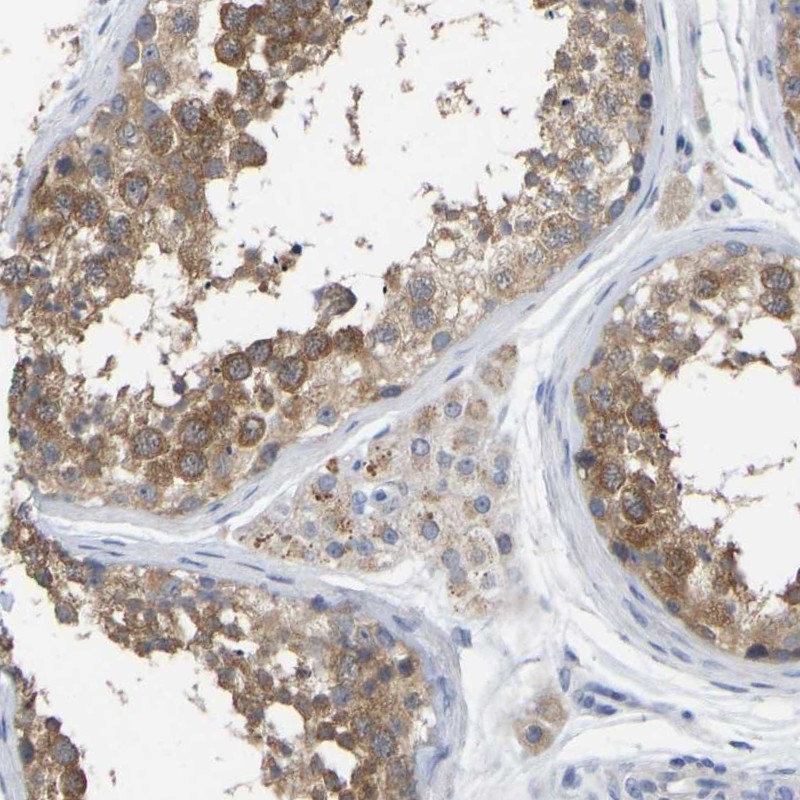

Immunohistochemical staining of human testis shows cytoplasmic positivity in cells in seminiferous ducts and Leydig cells.